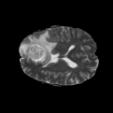

To better retain the deep features of an image and solve the sparsity problem of the end-to-end segmentation model, we propose a new deep convolutional network model for medical image pixel segmentation, called MC-Net. The core of this network model consists of four parts, namely, an encoder network, a multiple max-pooling integration module, a cross multiscale deconvolution decoder network and a pixel-level classification layer. In the network structure of the encoder, we use multiscale convolution instead of the traditional single-channel convolution. The multiple max-pooling integration module first integrates the output features of each submodule of the encoder network and reduces the number of parameters by convolution using a kernel size of 1. At the same time, each max-pooling layer (the pooling size of each layer is different) is spliced after each convolution to achieve the translation invariance of the feature maps of each submodule. We use the output feature maps from the multiple max-pooling integration module as the input of the decoder network; the multiscale convolution of each submodule in the decoder network is cross-fused with the feature maps generated by the corresponding multiscale convolution in the encoder network. Using the above feature map processing methods solves the sparsity problem after the max-pooling layer-generating matrix and enhances the robustness of the classification. We compare our proposed model with the well-known Fully Convolutional Networks for Semantic Segmentation (FCNs), DecovNet, PSPNet, U-net, SgeNet and other state-of-the-art segmentation networks such as HyperDenseNet, MS-Dual, Espnetv2, Denseaspp using one binary Kaggle 2018 data science bowl dataset and two multiclass dataset and obtain encouraging experimental results.